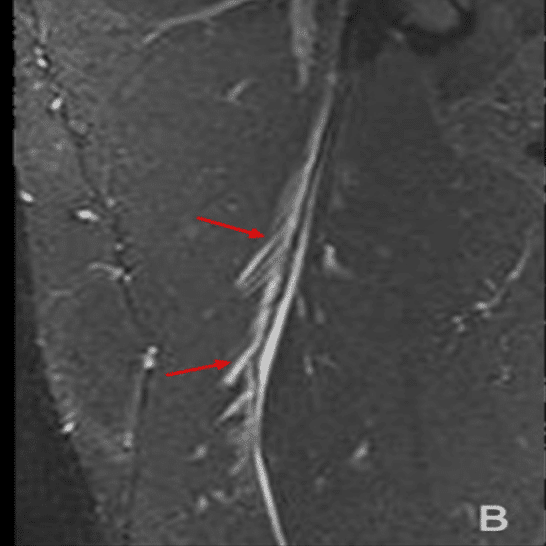

・Ⅱ型3度

(Pedret C, J Belg Soc Radiol. 2022から引用)

全周性に腱膜の連続性が確認できない

(奥脇 透:大腿二頭筋肉ばなれの MRI 分類、臨床スポーツ、2019より引用)